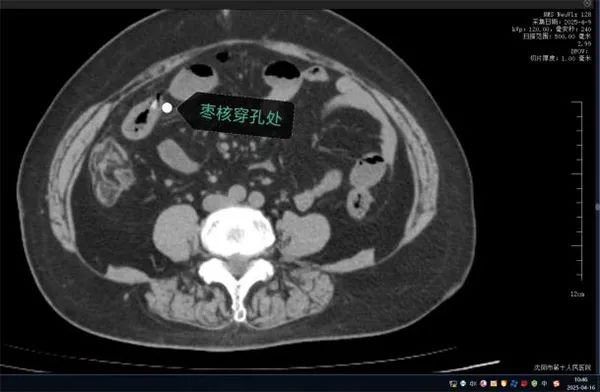

无独有偶,63岁的康阿姨近日因突发“刀绞般”剧烈腹痛,深夜被紧急送往沈阳市第十人民医院。短短数小时内,她出现高热、腹肌强直等弥漫性腹膜炎症状。CT检查显示腹腔游离气体,高度怀疑消化道穿孔。

家属回忆,当天上午康阿姨吃粽子时误吞两颗枣核。医生会诊判断枣核尖端已刺穿小肠,紧急手术取出异物。

图源:沈阳市第十人民医院